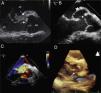

A) Ecocardiografía transesofágica con vegetación en válvula mitral y aórtica (flechas). B) Cabeza de flecha muestra la conexión fistulosa. Asterisco a nivel del seudoaneurisma de la pared aórtica. C) Doppler color al mismo nivel que imagen B que muestra la conexión fistulosa entre la aorta y la aurícula izquierda. D) Ecocardiografía transtorácica tridimensional que muestra la fístula (flecha) entre la aorta y la aurícula izquierda.

AI: aurícula izquierda; Ao: aorta; VI: ventrículo izquierdo.

Presentamos el caso de un niño de 10 años sano, que acude por fiebre elevada y cefalea. Destaca a la exploración alteración del nivel de conciencia, rigidez nucal y soplo sistólico plurifocal ii/vi. La analítica muestra leucopenia 1.200/μl, neutropenia 610/μl y proteína C reactica de 22mg/dl. La radiografía de tórax y el electrocardiograma resultan normales. Ante la sospecha de meningoencefalitis, se inicia tratamiento empírico con cefotaxima por vía intravenosa, no realizándose punción lumbar por inestabilidad hemodinámica que precisa soporte vasoactivo. Tras 6 días de tratamiento persiste febril; el hemocultivo resulta positivo a estafilococo aureus y se cambia antibioterapia a cloxacilina y gentamicina que continúa durante 6 semanas. La ecocardiografía transtorácica (ETT) mostró vegetaciones en el velo septal de la válvula mitral y en el seno coronariano derecho de la válvula aórtica, con insuficiencia mitral y aórtica moderada con aumento de la ecogenicidad en la unión auriculoventricular, que se confirma en la ecocardiografía transesofágica (ETE) (fig. 1 A). Queda afebril al octavo día de tratamiento y un mes después del alta hospitalaria presenta un soplo continuo en borde esternal. La ecocardiografía mostró un trayecto fistuloso entre la aorta y la aurícula izquierda, y la formación de un seudoaneurisma del seno de Valsalva no coronariano sin presencia de vegetaciones (fig. 1 B).